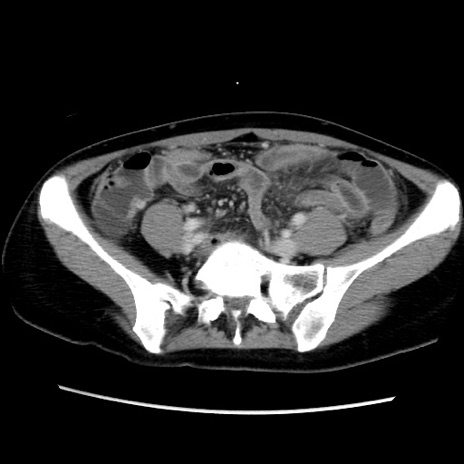

【症例】40歳代女性

【主訴】上下腹部痛

【現病歴】2日目から下腹部痛あり。夜間は痛みで眠れなかった。昨日より上腹部痛と下痢が出現。臥位で痛みは軽快したため、休んでいた。本日になって臥位でも立位でも痛みが強くなってきたため救急要請。

【既往歴】子宮内膜症

【身体所見】部:平坦・軟、左上下腹部に圧痛あり、反跳痛あり。

【データ】WBC 21800、CRP 26.78